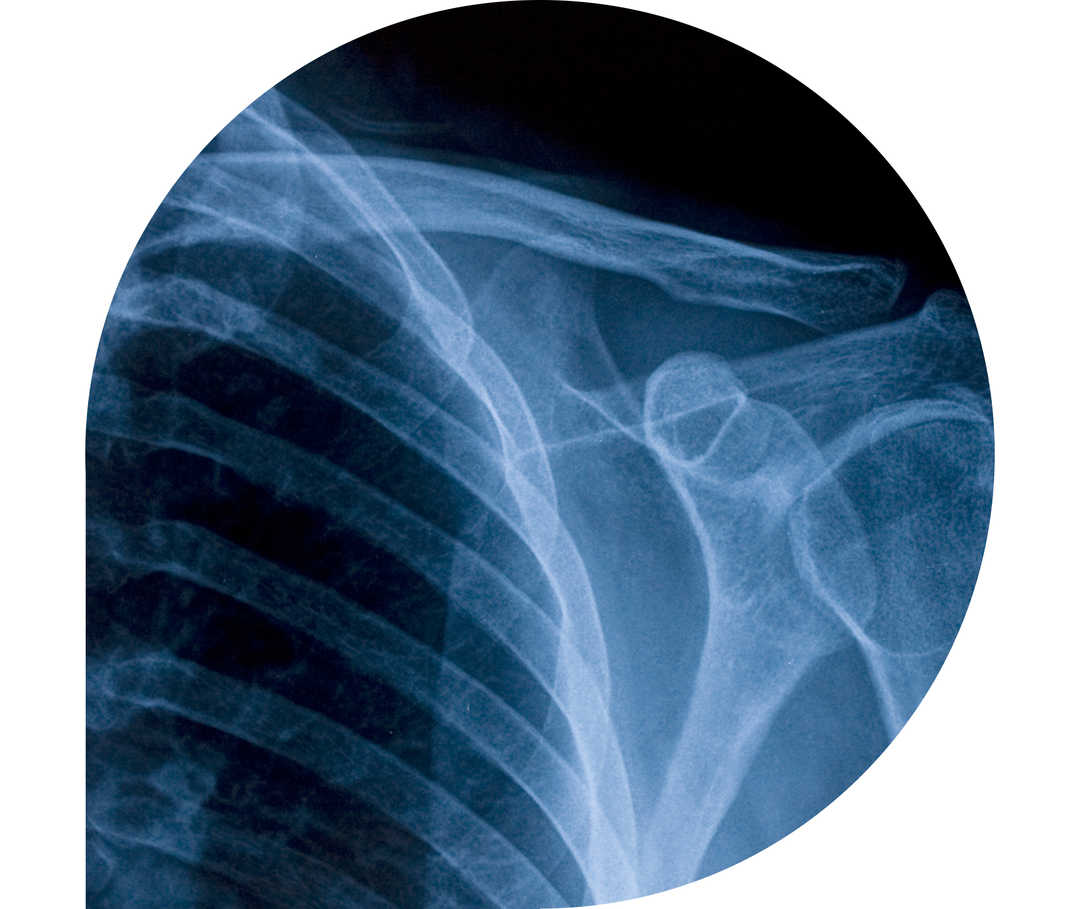

Ratgeber Rheuma: Schulter/Nacken-Skelett im Röntgenblick

Die Polymyalgia rheumatica (PMR) ist eine entzündlich-rheumatische Erkrankung. Direkt übersetzt bedeutet sie „Vielmuskelschmerz“. Die dabei auftretenden Entzündungen der Schulter-, Rücken- und Nackenmuskulatur führen zu Schmerzen und Steifheit in den jeweiligen Regionen. Auch die Hüftmuskulatur kann betroffen sein. Die Polymyalgia rheumatica ist der Riesenzellarteriitis sehr ähnlich, häufig treten beide Erkrankungen sogar zusammen auf. Forscher*innen sind sich nicht einig, ob es sich überhaupt um zwei unterschiedliche Krankheiten handelt oder Polymyalgia rheumatica und Riesenzellarteriitis nicht Folgen desselben Krankheitsprozesses sind. Aus diesem Grund wird die Polymyalgia rheumatica häufig auch zu den Vaskulitiden (durch eine Fehlsteuerung des Immunsystems ausgelöste Gefäßentzündungen) gezählt.1,2,3,4,5